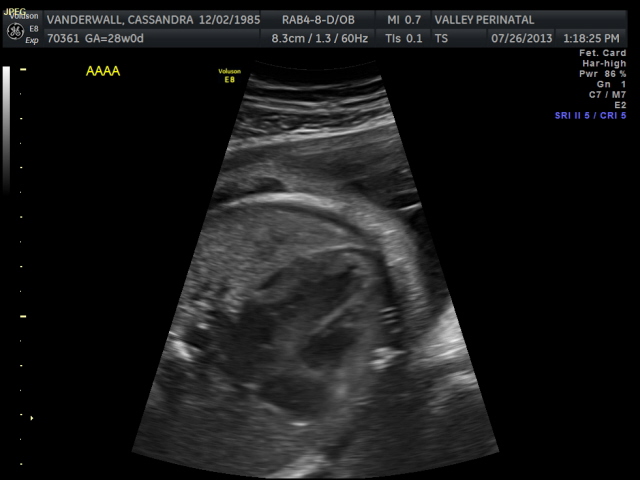

Friday we surpassed yet another milestone! The babies have been cooking for 7 months, which means we are now above the average gestational age for quintuplets. All of the babies were measured on Friday and they are all measuring within a day or two of the recommended size for babies at this point in pregnancy.

The weight of each baby is estimated based on the length of the baby’s humerus (bone in upper arm) and femur (bone in upper leg), the circumference of their abdomen and their head circumference.

The biggest one in the bunch is Baby B at 2lbs and 12oz at the 62nd percentile. Little Elle Rose (Baby E) is the munchkin, but not by much as baby D and Theo (baby A) are also the same weight (2 ½ lbs) but just a bit longer. At this rate, when the baby’s are measured again at 32 weeks they will be about 1lb heavier each. Let’s just hope this Mama can keep up!

All of their organs (kidneys, bladders, hearts, brains, stomachs) look great and are also appropriate sizes. The blood flow to Elle has improved and has stabilized. All heart rates remain within normal limits, and are often on the higher side, which is probably because they just can’t sit still. We are truly excited to meet our little wiggle worms!